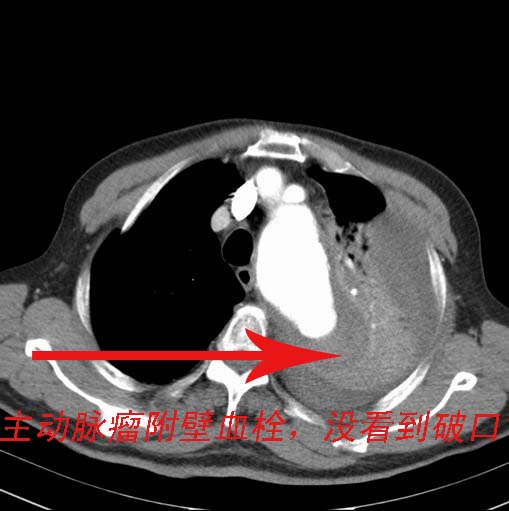

标题: CT27522:主动脉瘤CT增强扫描

男、72、胸痛、咯血二天。

主动脉ct增强扫描,请问是否有破裂出血,ct未见明显破口,但是胸腔积液较昨天ct明显增多,密度增高,ct值达47hu左右。请大家帮助会诊。

夹层ao瘤,并附壁血栓形成。

真性主动脉瘤,伴有破裂,无明确夹层动脉瘤征。

主动脉瘤伴附壁血栓。左侧胸腔积液,左肺段性肺不张。如果破裂,病人的症状应该很严重。